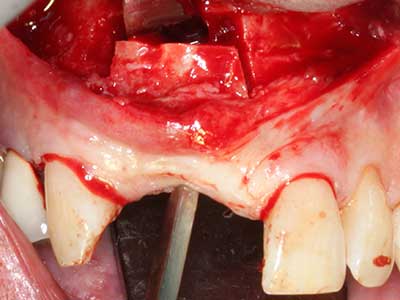

Si es preciso realizar intervenciones quirúrgicas en las que el hueso está en contacto directo con estructuras sensibles, como son los vasos sanguíneos o los nervios, los instrumentos rotativos presentan un enorme potencial de provocar lesiones iatrogénicas. Así, precisamente en la representación de nervios después de una lesión iatrogénica, o en el transcurso de la lateralización de un nervio para resecciones, reconstrucciones o incorporación de implantes, los equipos piezoeléctricos pueden resultar muy útiles para preparar la tapa ósea y retirar las partes de tejido duro cercanas al nervio (fig. 17-20). Por lo general, un ligero contacto del cordón nervioso con el inserto piezoeléctrico no tiene consecuencia alguna; ahora bien, un procedimiento poco cuidadoso con movimientos tipo sierra o piezas de trabajo sobre la base ósea aún existente puede provocar lesiones nerviosas temporales o incluso permanentes. Con todo, el riesgo de sufrir una lesión de este tipo se considera significativamente inferior que en los casos en los que se utilizan sierras y fresas (Pereira, Gealh et al. 2014).